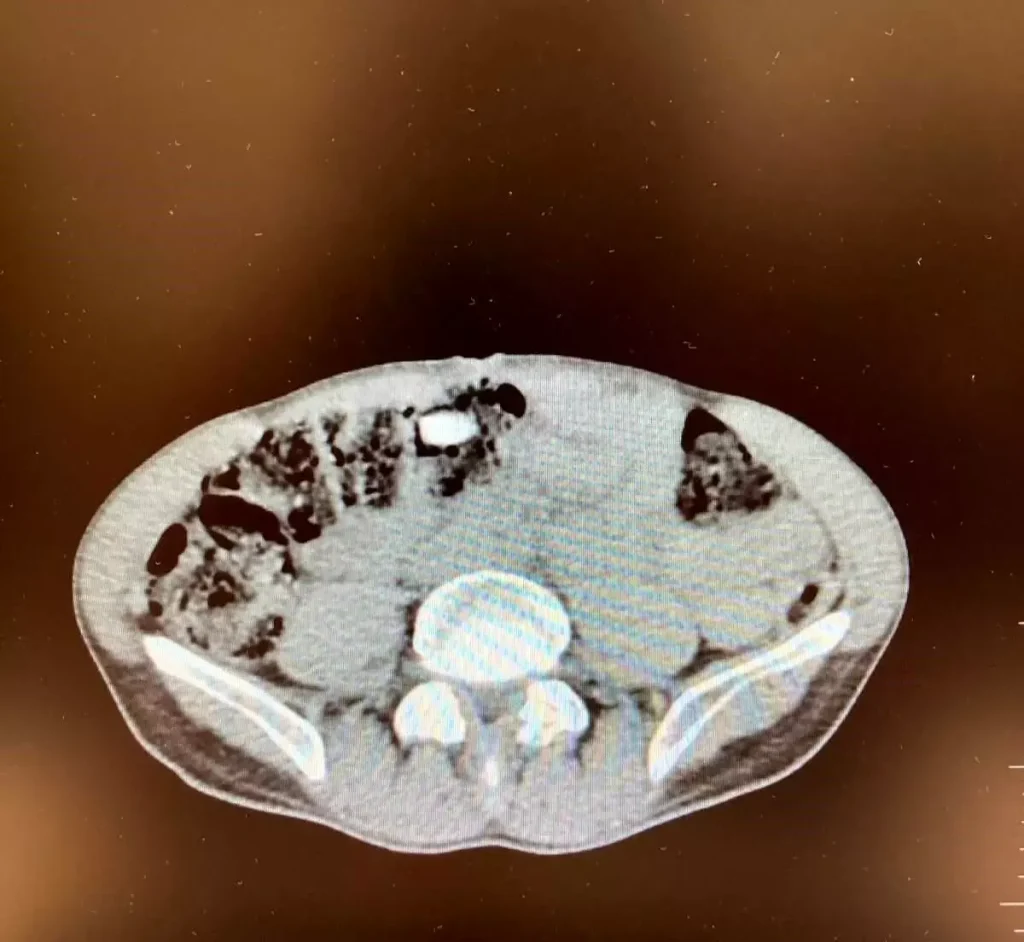

Denizli İl Emniyet Müdürlüğü Narkotik Suçlarla Mücadele Şube Müdürlüğünce uluslararası uyuşturucu madde ticaretinin önlenmesine yönelik çalışmalar devam ediyor. Yapılan incemeler ve değerlendirmeler sonucunda Denizli’ye havayoluyla yolculuk eden yabancı uyruklu şahsın uyuşturucu madde getireceği tespit edildi. Şüpheli, Narkotik Suçlarla Mücadele Şube Müdürlüğü ve Çardak Havalimanı Gümrük Muhafaza Bölge Amirliği görevlilerince müşterek yapılan çalışmalar neticesinde yakalandı. Şüphelinin eşyalarında yapılan aramalarda 6 parça halinde giysilere emdirilmiş şekilde 1 kilo 257 gram metamfetamin maddesi ele geçirildi. Yapılan iç beden muayenesinde ise 3 parça halinde 15 adet ecza hap ele geçirildi. “Uyuşturucu veya uyarıcı madde ticareti yapmak” suçundan adli makamlara sevk edilen şüpheli, tutuklanarak cezaevine gönderildi. – DENİZLİ